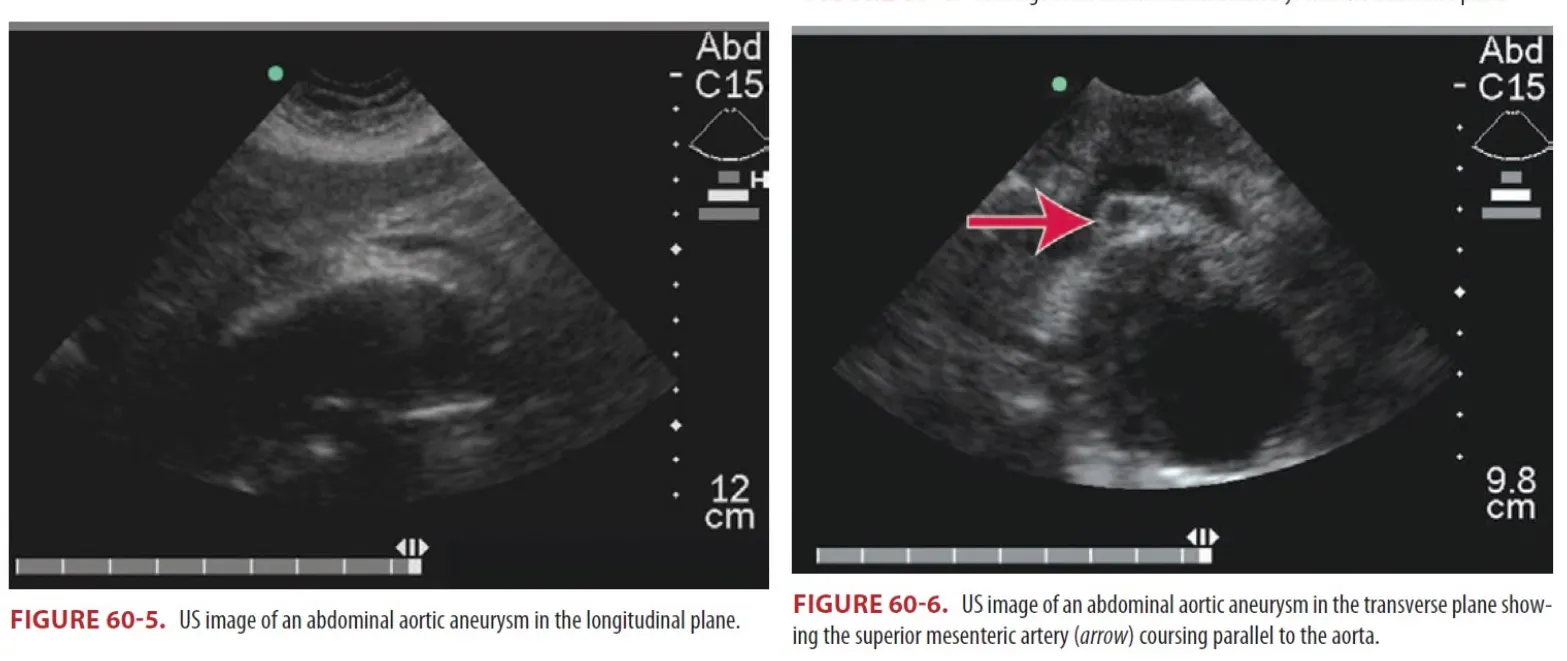

(1) Unstable한 환자의 경우 응급실을 나가서는 안 되고 bedside US가 image of choice이다.

① Bedside US는 ideal initial screening.

② Aneurysm을 확인하고 크기를 평가하는데 90% 초과의 민감도를 가짐

③ 3cm 미만의 aortic diameter는 acute aneurysmal disease를 배제할 수 있다.